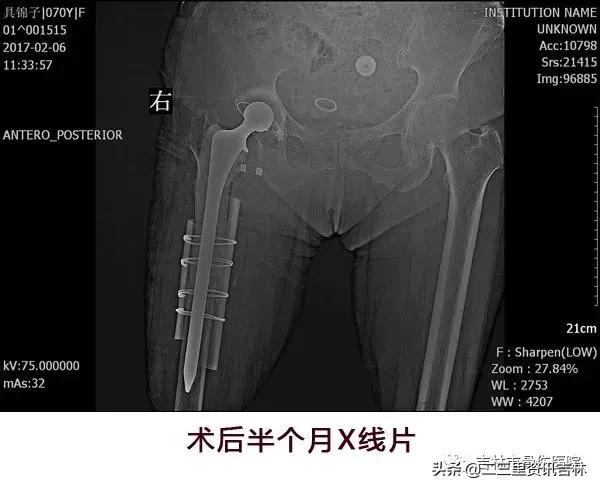

该患于2008年6月因“右股骨颈骨折”在外院行“右侧髋关节置换术”,术后恢复良好,休养至今,于2016年11月30日在自家走路时不慎滑倒摔伤,伤后出现右髋部肿痛,不敢活动,未经处置,在家休养至今未见缓解,现为求系统治疗前来我院就诊,经门诊医生查体拍片后以:“右侧髋关节置换术后假体周围骨折”收入院。

患者入院后给予常规检查,经三级医师查房,临床诊断确诊,查无明显手术禁忌症后在腰硬+全麻麻醉下行“右侧髋关节置换术后假体周围骨折关节翻修术”,术后抗感染、消肿、抗凝、关节功能松动练习等对症治疗,术后患者恢复良好。